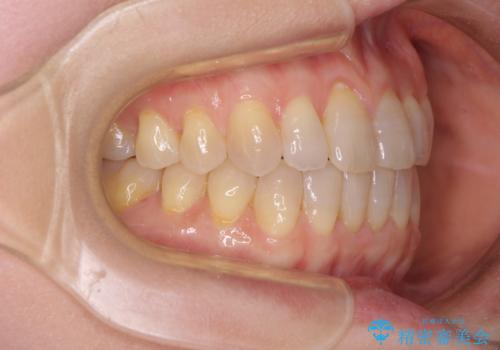

前歯の叢生と切端咬合 インビザラインによる矯正治療

- 前歯のデコボコを気にして来院された患者様です。

上下前歯の先端同士が接触する切端咬合であったため、上顎は歯列を拡大し、下顎はIPR(歯と歯の間を削る)により叢生を解消しながら歯列を小さくすることとしました。

治療前から歯肉退縮が認められ、矯正治療により悪化する可能性が考えられたため、無理のない歯の移動と頻繁な経過観察を行いました。

切端咬合はスムーズに解消され、前歯の負担を軽減させることができました。